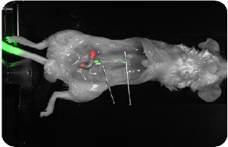

| 完整解决方案 美国Li-COR Biosciences公司的Pearl™ Licor小动物成像系统整合Odyssey双色红外激光成像系统组成体内和体外的多功能成像平台。该平台的体内成像或体外成像均使用该公司研发的、行业领先的IRDye染料,保证体内体外成像结果的可比性。目前,没有其他成像系统能够满足在体内和体外成像均使用同一种染料开展研究工作。 ■ 红外光学试剂 肿瘤试剂 926-08446 IRDye® 800CW EGF Optical Probe 926-08946 IRDye 800CW 2-DG Optical Probe 926-09889 IRDye 800CW RGD Optical Probe 结构试剂 926-09375 IRDye® 800CW BoneTag™ (40 nmol) 926-09376 IRDye 680 BoneTag (80 nmol) 标记染料 929-70020 IRDye 800CW NHS Ester 929-80020 IRDye 800CW Maleimide 929-70010 IRDye 700DX NHS Ester 929-90010 CellVue Burgundy 929-90020 CellVue NIR815 ■ 应用 肿瘤成像-IRDye 800CW EGF Optical Probe 许多肿瘤(肾细胞癌、非小细胞肺癌、神经胶质瘤、卵巢癌、膀胱癌、胰腺癌、结肠癌和乳腺癌等)的发生都会出现EGFR过量表达, IRDye 800CW EGF 探针是EGFR的定把探针,该标记探针和EGFR结合,可以示踪肿瘤的发生和转移等。 IRDye 800CW EGF示踪的是前列腺肿瘤(绿),IRDye 680 BoneTag探针表示骨骼结构(红)。 Imaging data taken usingLI-COR’s Pearl™ Imager。 |